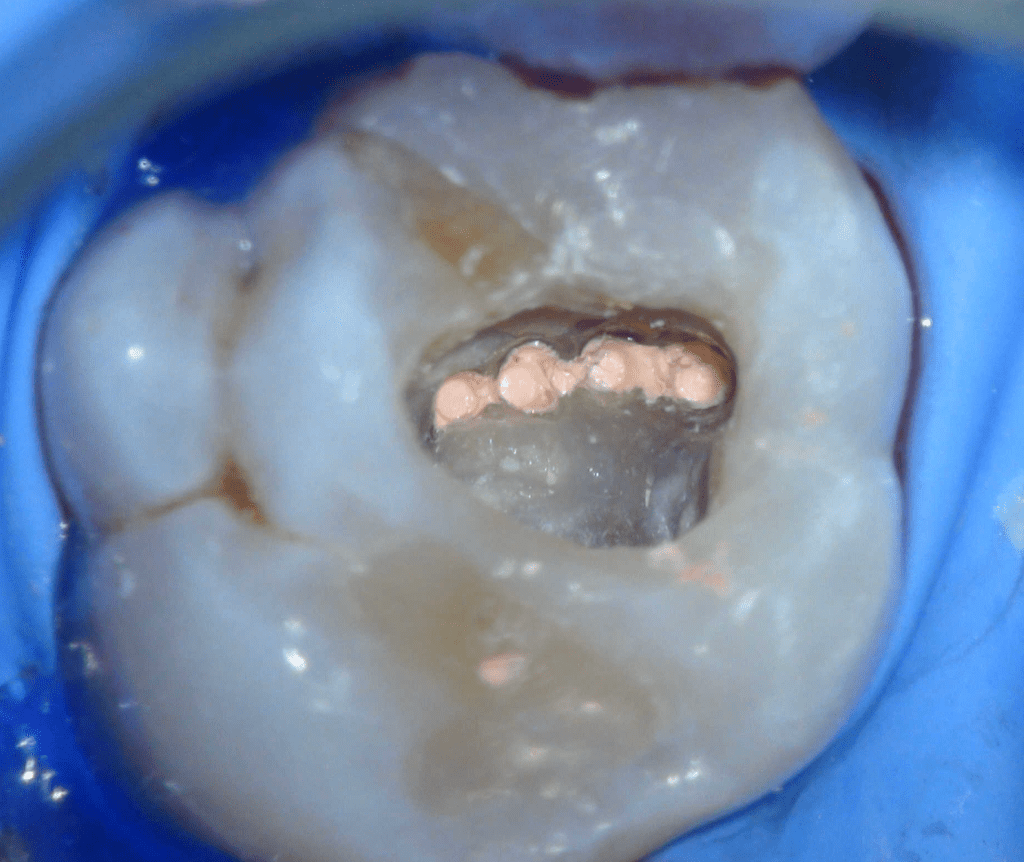

Reco preendo + 4 conductos molar superior